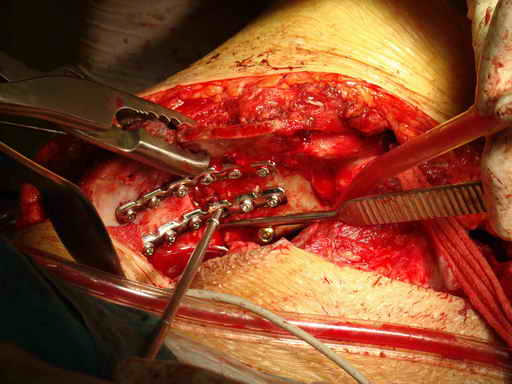

Остеосинтез подвздошной кости

Операционная. Оперирует д.м.н. проф. Казанцев А.Б.